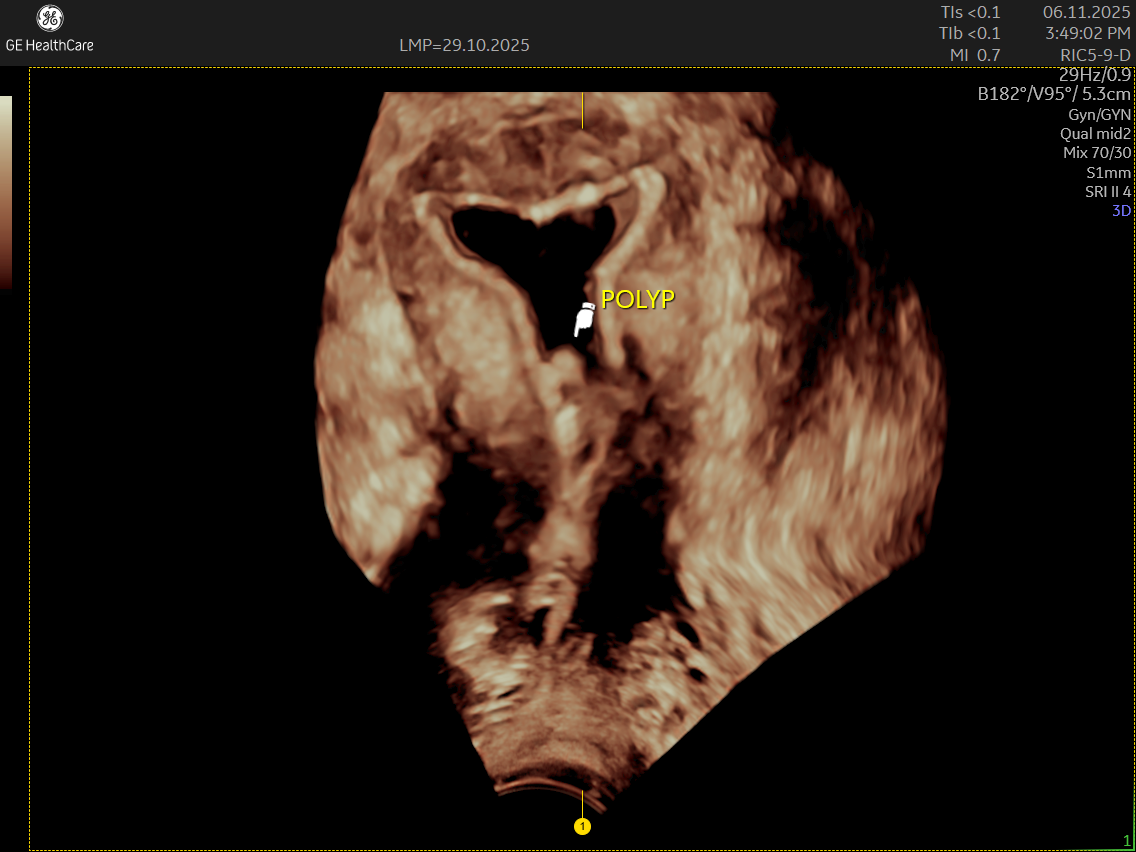

• Endometrial polyps

IMAGE GALLERY